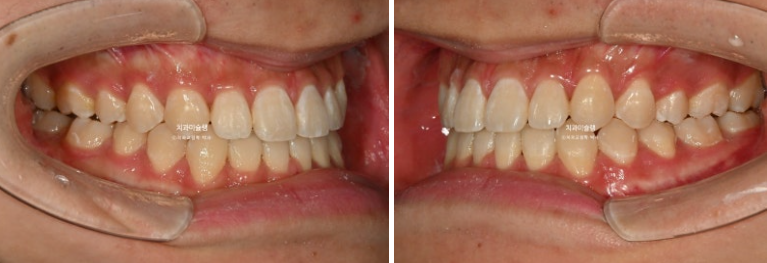

중심선이 어긋나있고 앞니 개방교합이 보입니다.

주걱턱으로 인해 앞니가 거꾸로 물리는 반대교합이 있습니다.

어금니 교합관계도 심한 3급입니다.

중심선은 정확히 맞으며 개방교합은 충분히 해소되었습니다.

반대교합은 개선되었고 교합관계는 1급을 달성

이제 전후 비교 보겠습니다.